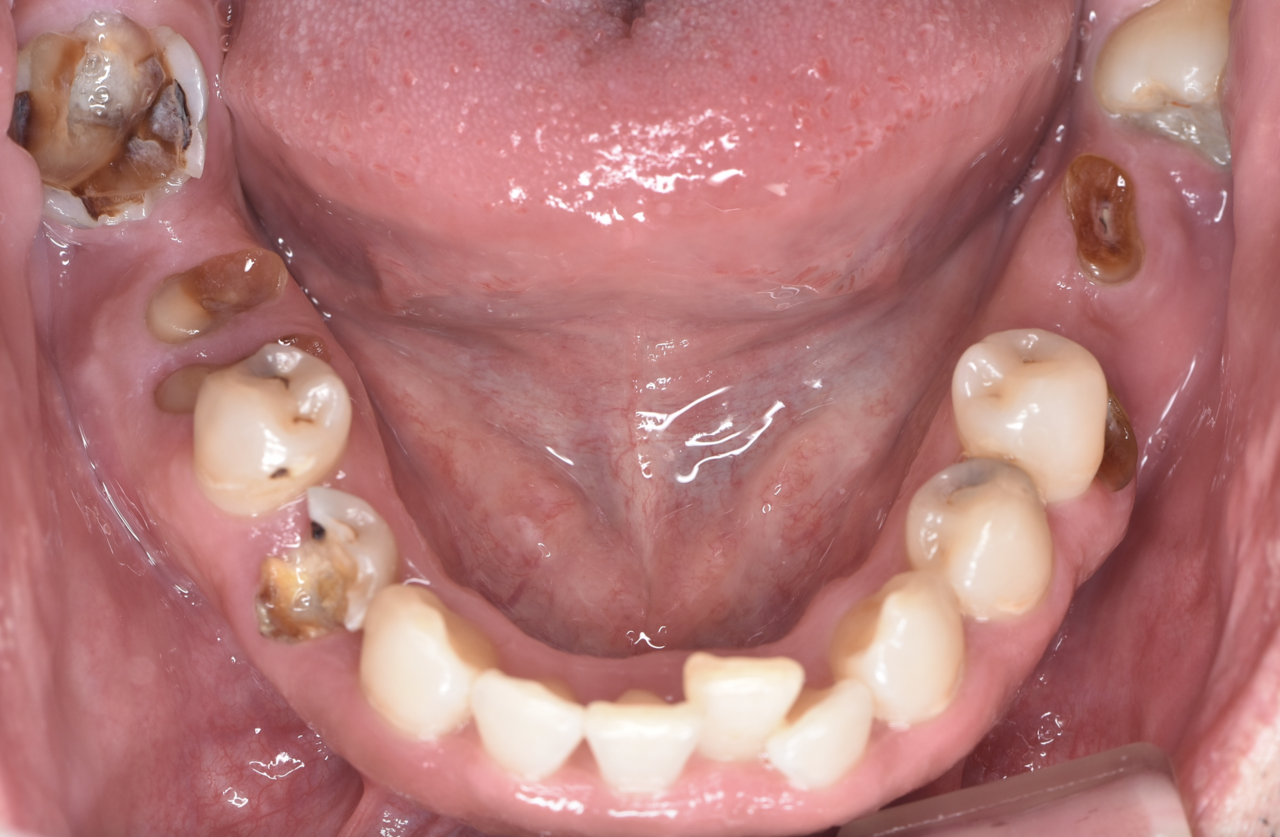

Before

40代女性 虫歯で再治療不可の部分をインプラントに

治療期間 4ヶ月 費用65万円

デメリット:費用が高い、外科処置が必要

After

骨が薄い部分に対してインプラント埋入と同時に

骨を足す処置(GBR)を行いました

*画像左上